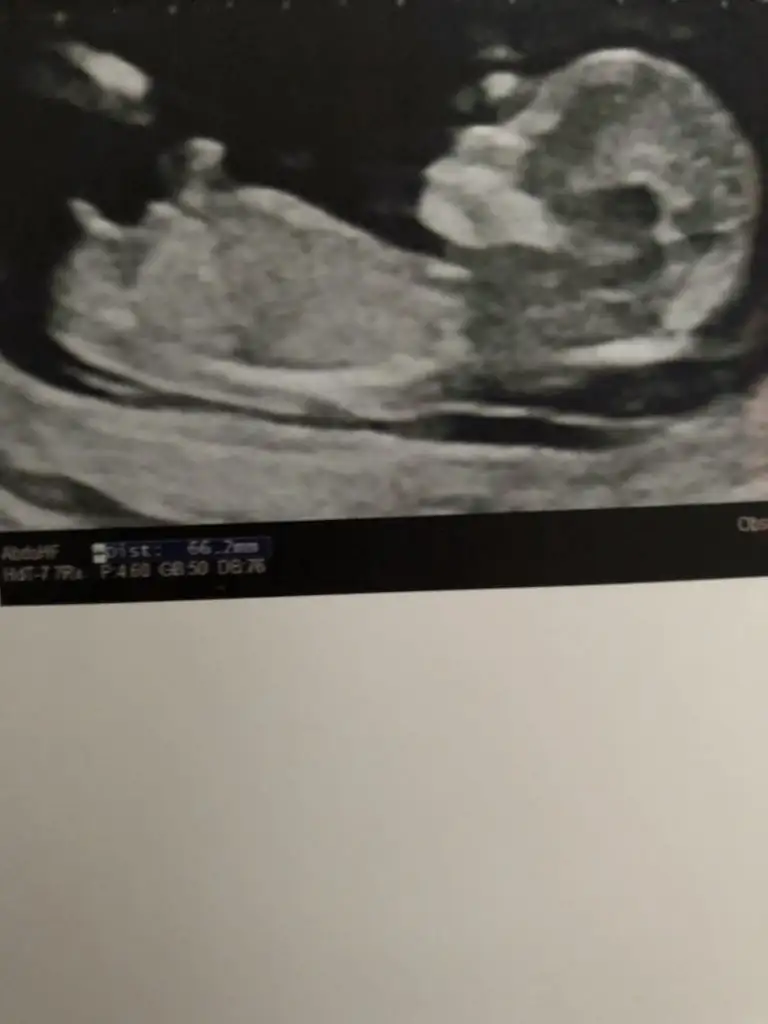

Erkek görünüyor gibi en iyi 11 12 13 haftalar olmalıCinsiyet tahmini yapabilirmisiniz 14 haftalik

Üsteki erkek altaki kız gibi sanki emin olamadımslm 12 haftalık ikiz gebelik banada tahminde bulunabilirmisniz